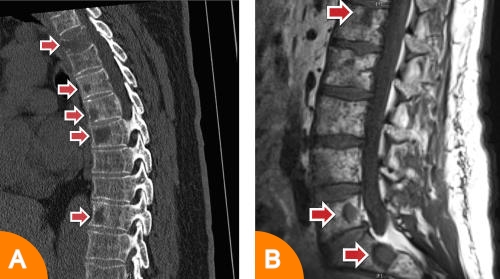

Der Einsatz bildgebender Verfahren dient an erster Stelle dem Nachweis von myelombedingten Knochen- und Knochenmarkveränderungen. Diese treten typischerweise in Form sogenannter Osteolysen (örtlich umschriebener Knochenauflösungszonen; Abbildung A) und fokaler Plasmazellansammlungen im Knochenmark auf (Abbildung 4B).

(Abbildung 4)

B) Darstellung von fokalen Läsionen in der Magnetresonanztomografie (MRT) der Wirbelsäule.

Ebenfalls häufig zeigt sich aber auch eine Osteoporose (diffuse Verminderung der Knochensubstanz) oder ein diffuser Befall des Knochenmarks.

Klassisches bildgebendes Verfahren war lange Zeit das konventionelle Röntgen zur Darstellung des Schädels, der Wirbelsäule, des Beckens sowie der langen Röhrenknochen (Oberarmknochen, Oberschenkelknochen), auch als "Pariser Schema" bezeichnet. Allerdings ist dieses Verfahren mit einer Reihe von Nachteilen bzw. Einschränkungen behaftet: Es ist relativ aufwendig und hat eine im Vergleich zu anderen Techniken schlechte Sensitivität (Empfindlichkeit). Darüber hinaus wird eine myelombedingte Knochenzerstörung oft erst sichtbar, wenn 30-50% der Knochensubstanz abgebaut ist. Aus diesem Grund kommen andere bildgebende Verfahren beim Multiplen Myelom bevorzugt zum Einsatz. Hierzu zählen die Computertomografie (CT), die sich besonders zur Beurteilung von Knochensubstanz bei Verdacht auf eine Instabilität des Knochens mit drohender Bruchgefahr (z.B. von Wirbelkörpern) eignet und die Magnetresonanztomografie (MRT), die besonders gut die nicht knöchernen Gewebe (z.B. Nervenstränge und Knochenmark) abbildet.